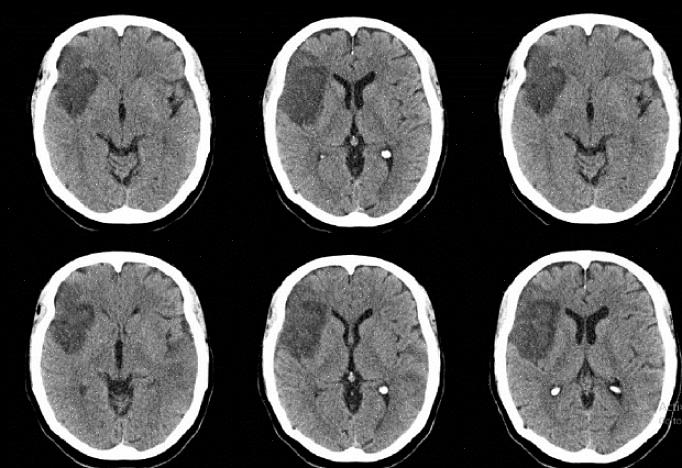

נוירולוגיות: הפרעות נוירווסקולריות, דמנציה של אלצהיימר, פגיעה קוגניטיבית קלה, גידולים, דמנציה פרונטו-זמנית, פגיעה מוחית טראומטית, עיוורון קליפת המוח, אפילפסיה וניוון קליפת המוח האחורי. -